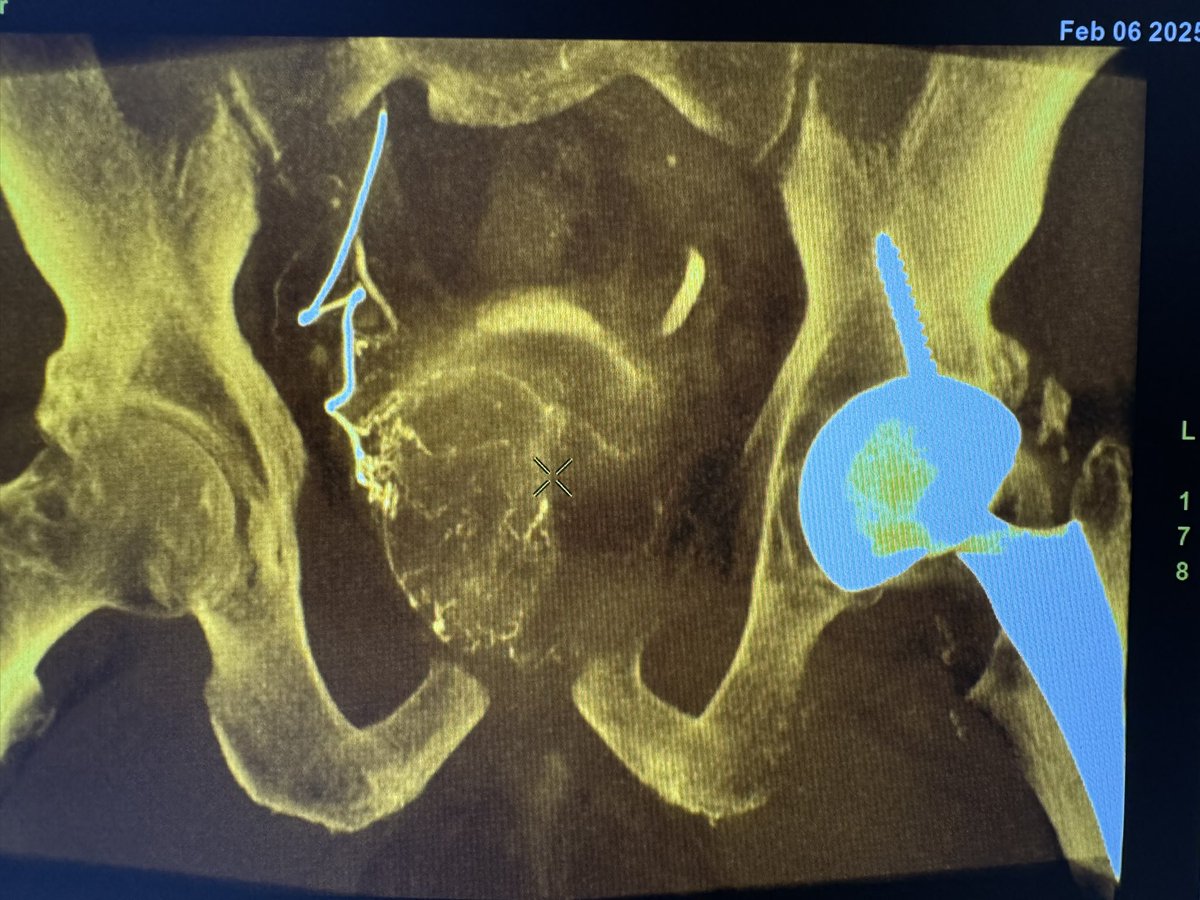

I found a unique variant quoted as 0.4% in an cadaveric anatomic studies. Was unable to find any angiographic images in the literature? Replaced inferior epigastric artery (yellow) off the obturator (blue) as a terminal branch of the internal iliac artery. Society of Interventional Radiology @BSIR